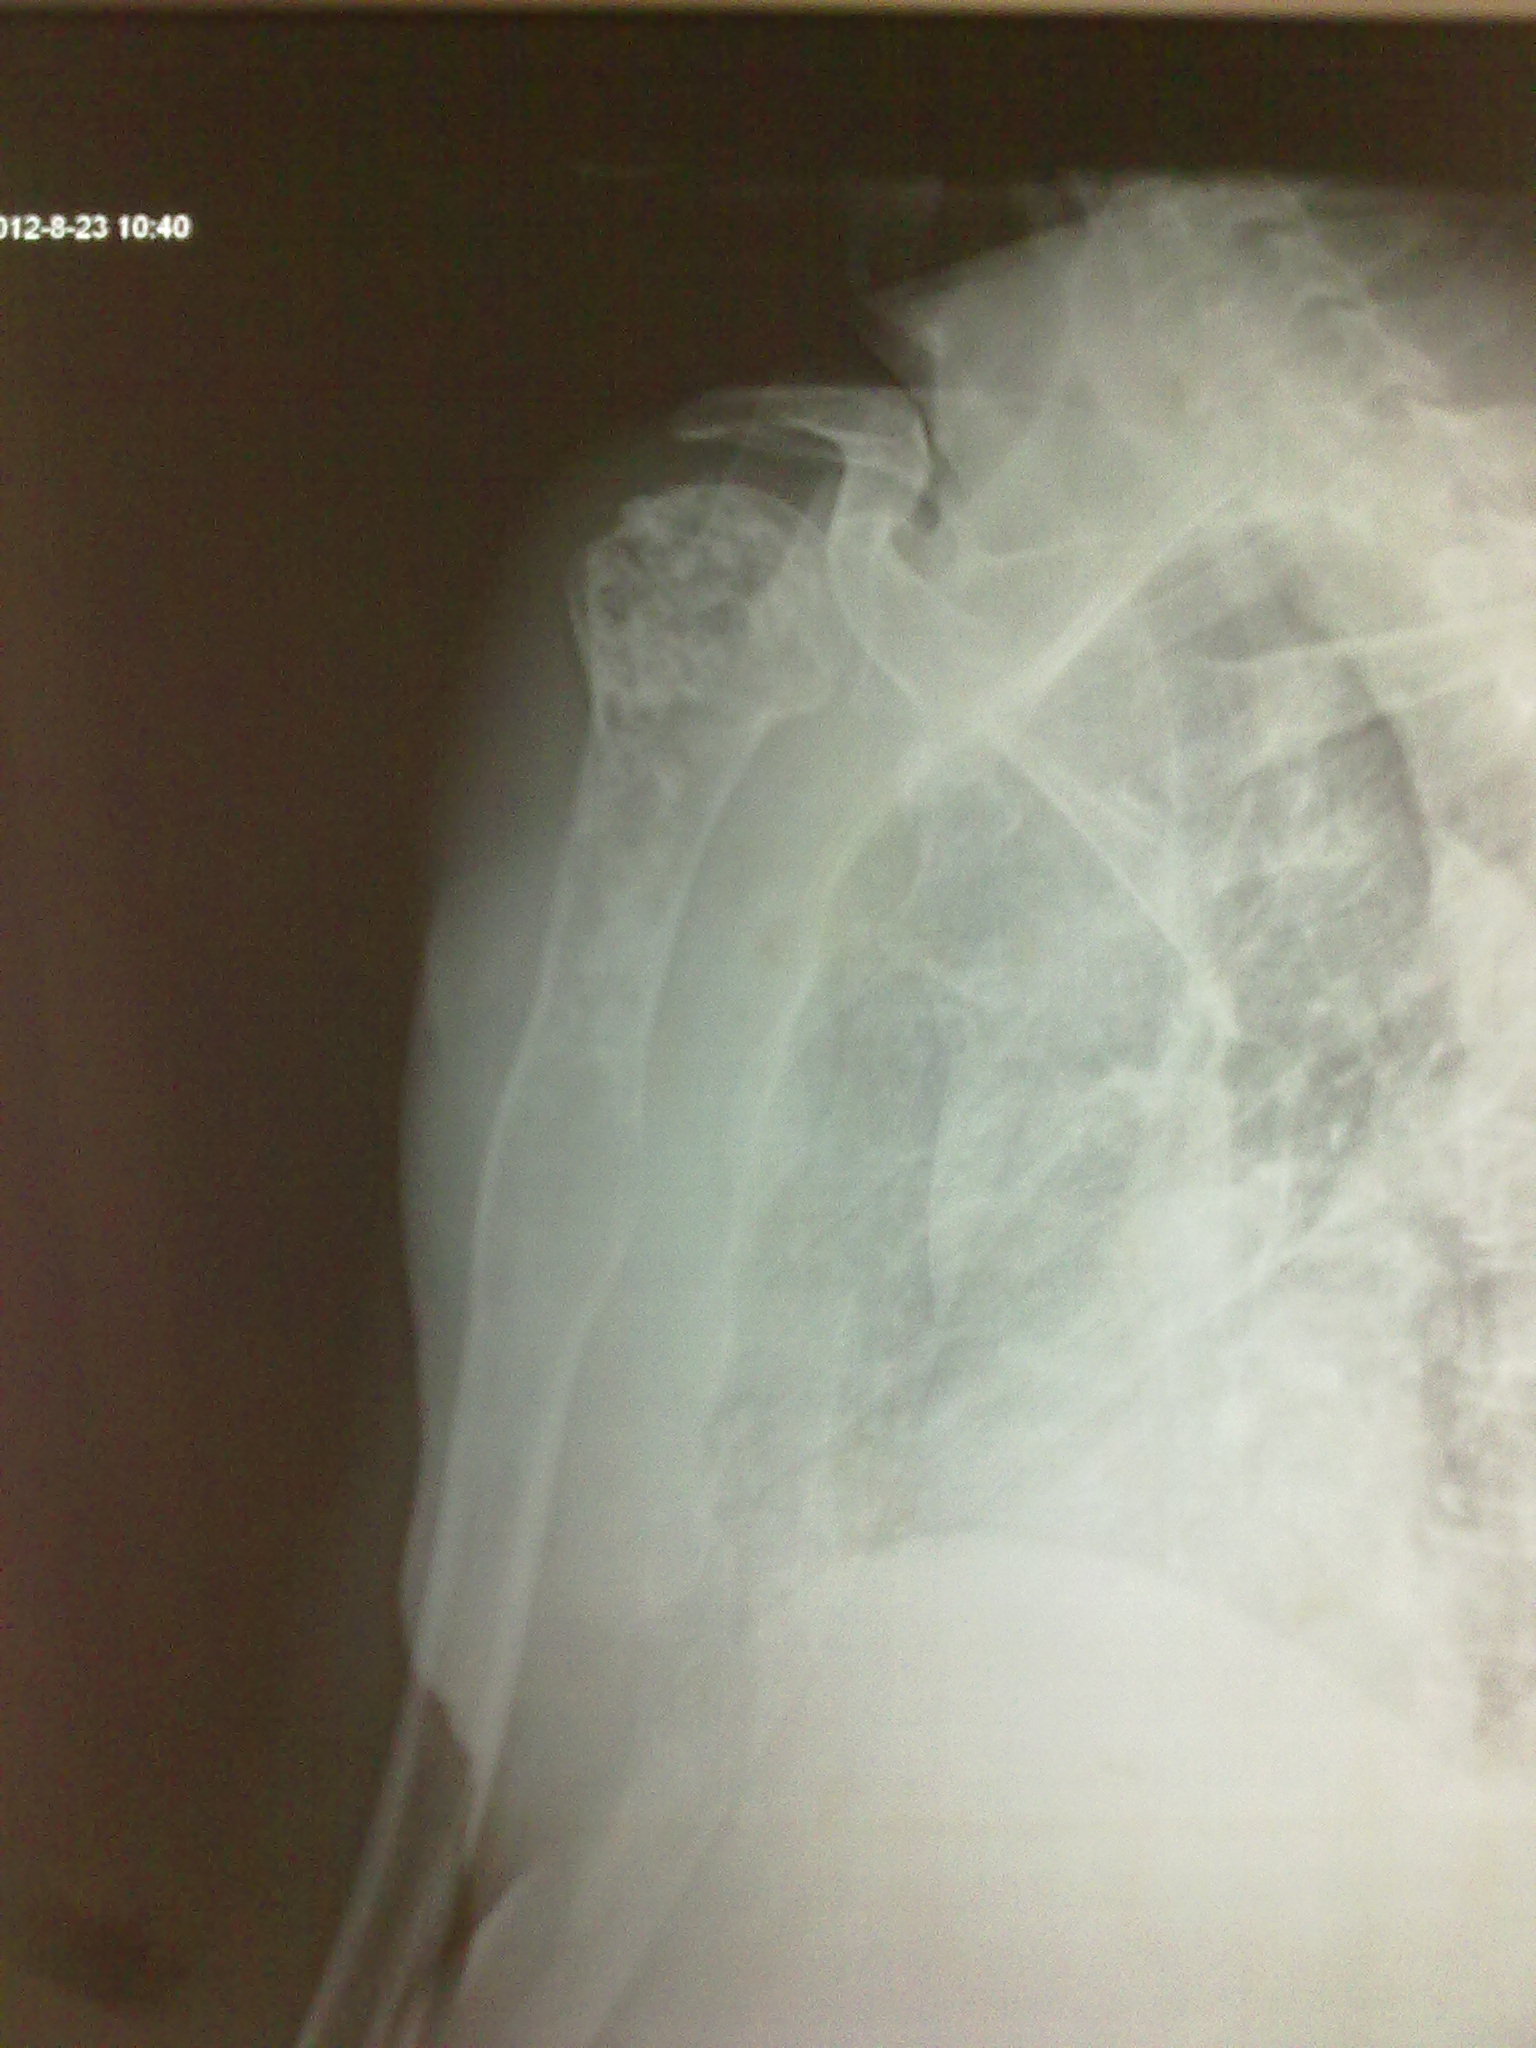

男,66岁,因疝气入院,常规检查发现右肱骨骨质破坏,

男,66岁,因疝气入院,常规检查发现右肱骨骨质破坏,素无症状、体征,请各位大师赐教。